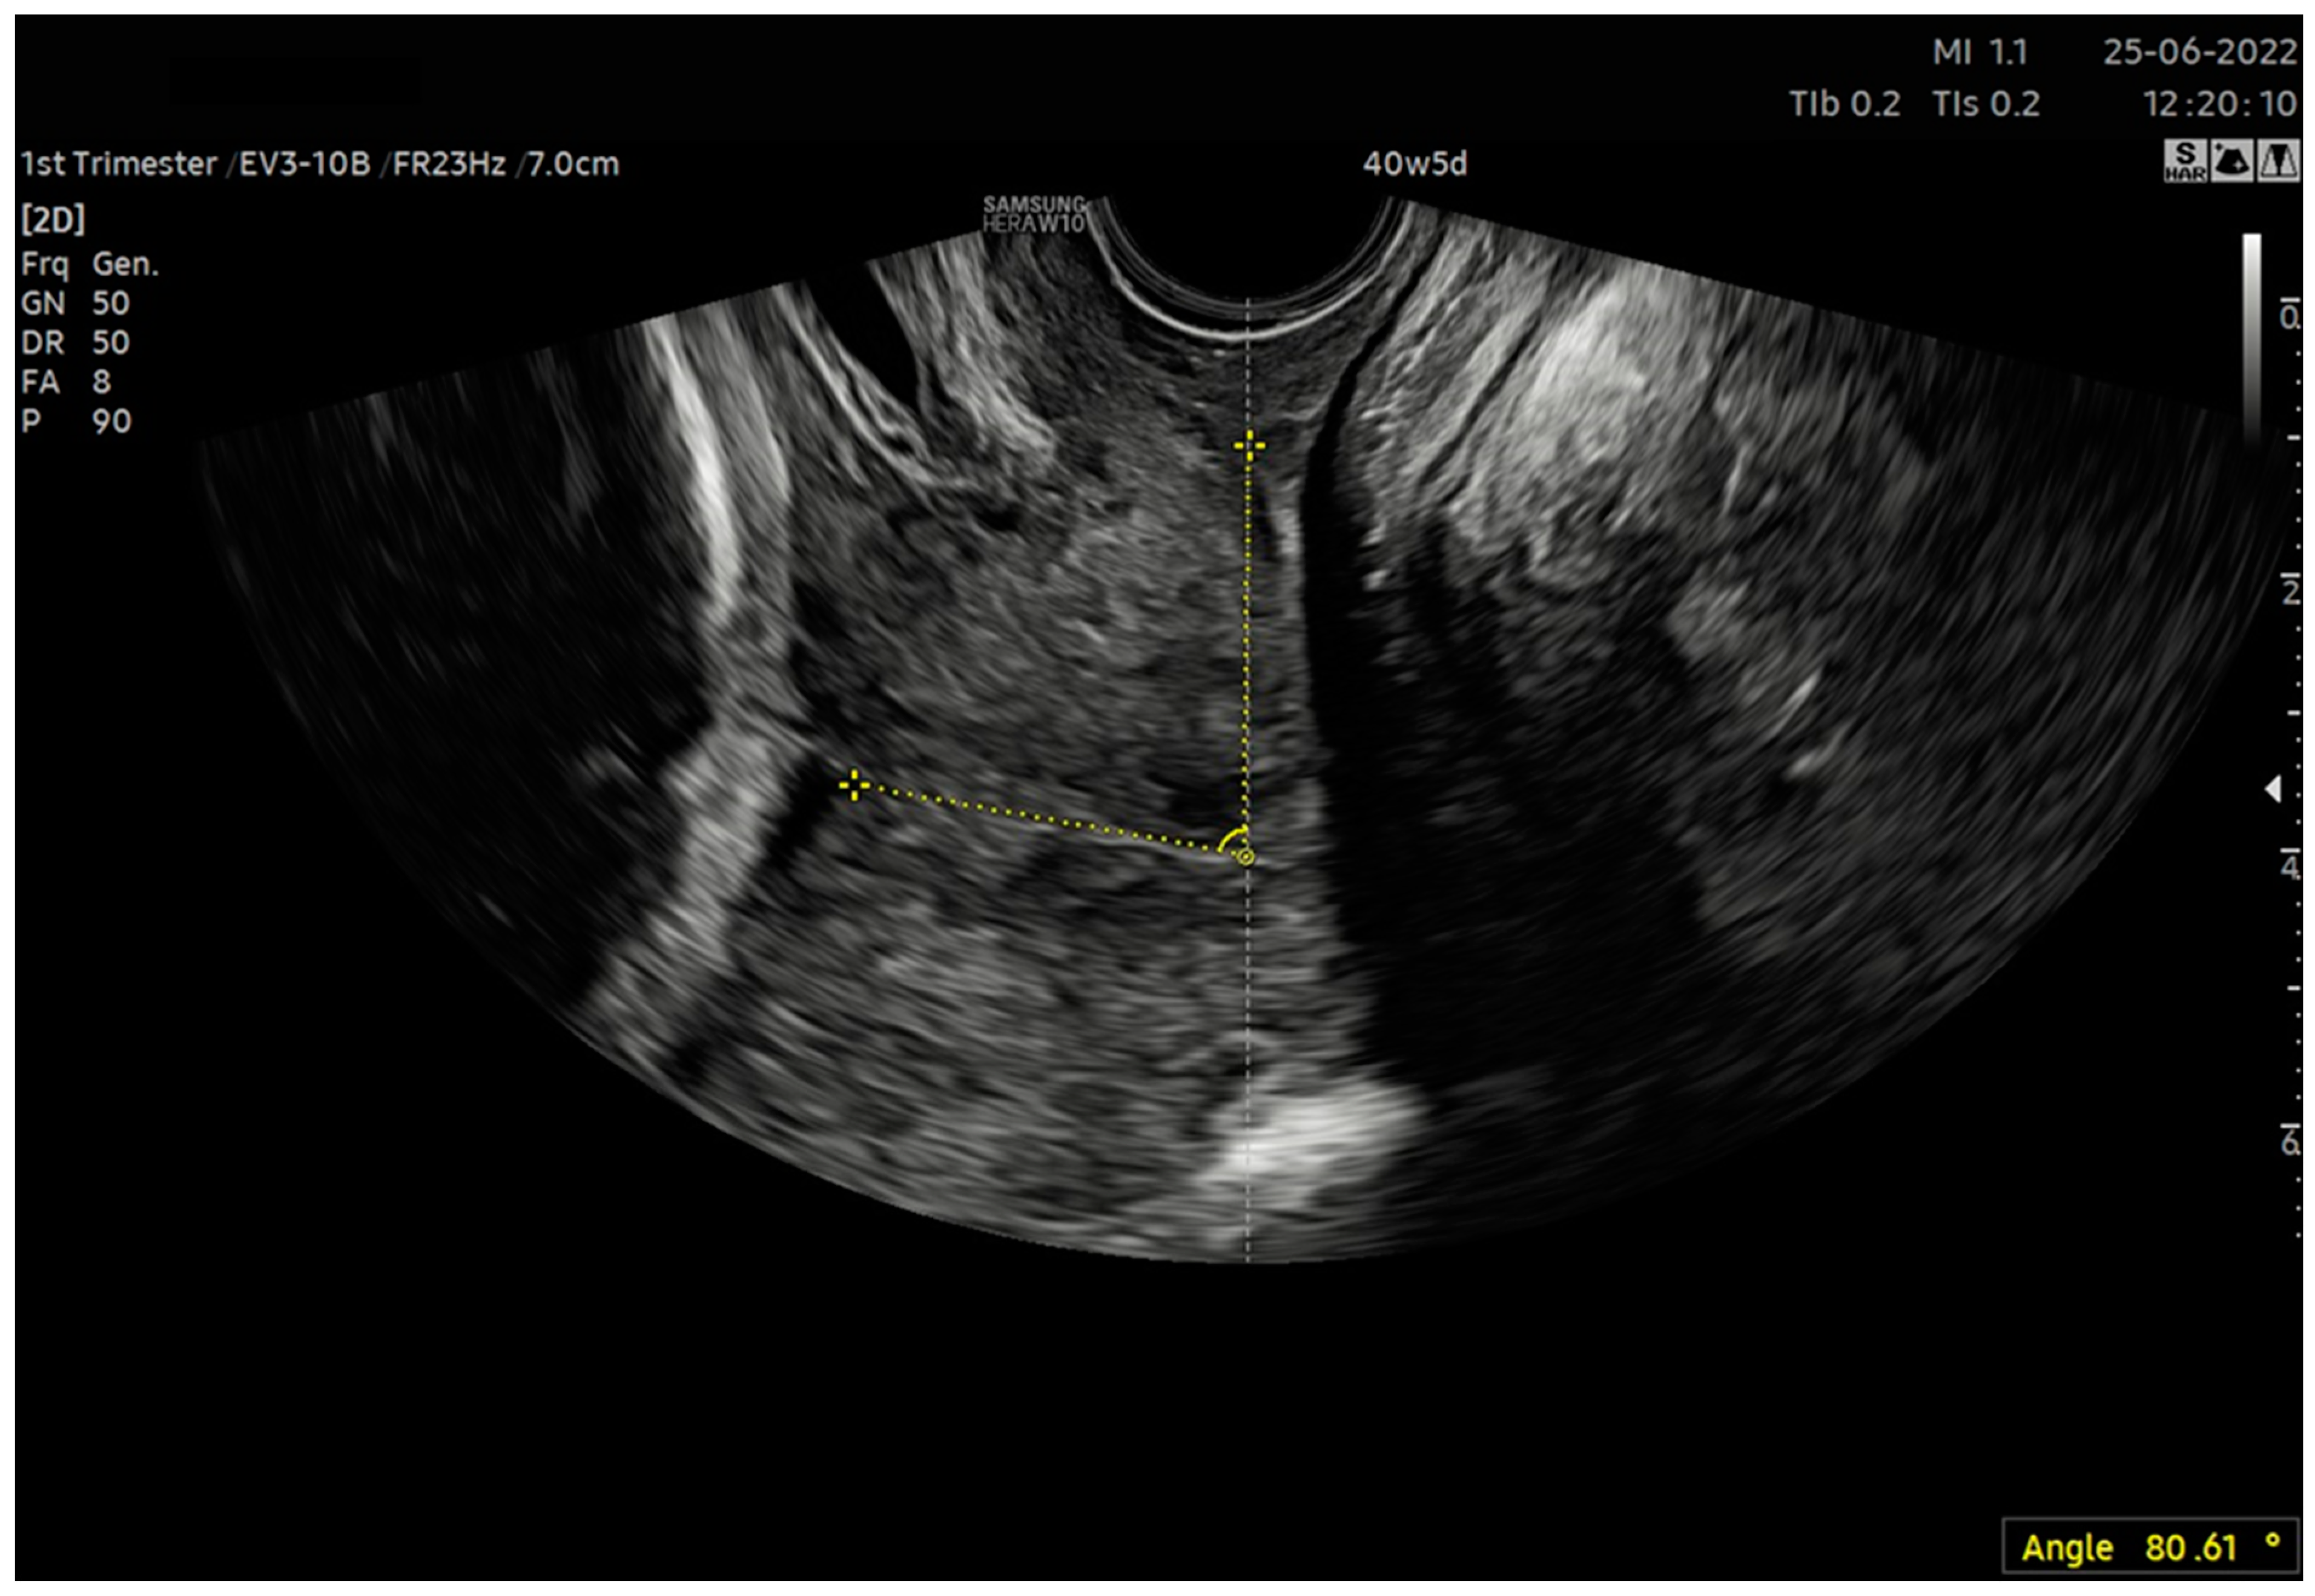

| 6. After calculating the E-Cervix parameters, volumetric image acquisition of the cervix was performed. The 3D image was rotated so that the external os of the cervix was presented en face on the screen; then, we measured the widest dimension of the external cervical os (dilatation—Figure 1). 7. We withdrew the transducer to the area of the vaginal os. 8. The transducer was placed in the vaginal axis; the vagino–cervical angle (VCA) measurement was performed after turning on the “central transducer line” option; the second line was guided tangentially to the axis of the cervical canal. In the case of a bent canal, the line was drawn tangentially to the end part contacting the vagina. We measured the angle formed at the intersection of the abovementioned lines (Figure 3). 9. We measured the AoP with the transducer located near the vaginal opening by drawing two lines—tangent to the long axis of the cross-section through the pubic symphysis and through the bone point of the fetal head being the most advanced in the birth canal (Figure 2). |